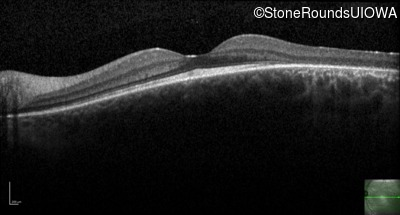

Age at visit: 34 years

OD OS